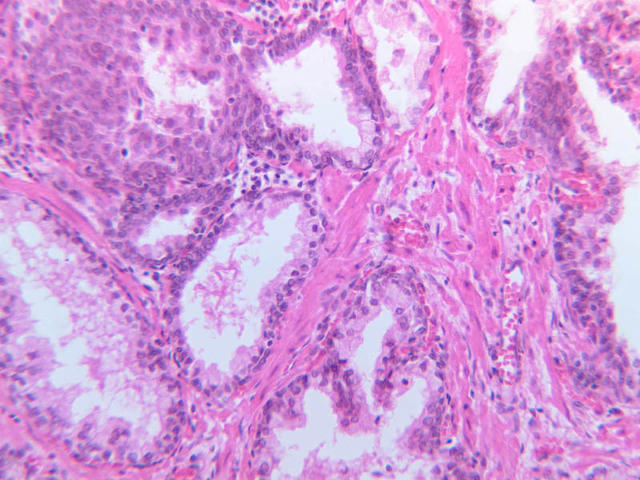

The prostate is an aggregate of numerous tubulo-alveolar glands embedded in a dense stroma of collagen fibers and smooth muscle (B-90 [2.5x, 10x, 20x, 40x-labeled]; B-91 [2.5x, 10x, [[http://www.medicalhistology.us/wiki/bin/viewfile/Main/ProstateImages?rev=1;filename=b91_prostate_adult_20x_he.jpg[20x]], 40x-labeled] [2.5x, 10x, 10x, 20x, 40x]). Note that the prostatic urethra, the portion of the urethra which runs through the prostate gland, is also present (B-91 [2.5x, 10x, 20x, 40x]). Under high dry magnification, it is obvious that the glandular epithelium varies from simple cuboidal to pseudostratified columnar. Prostatic acini often contain eosinophilic corpora amalacea (prostatic concretions) (B-90 [2.5x, 10x, 20x, 40x-labeled]). The number and degree of calcification of these spherical, lamellated structures increase with age. In some sections, the prostatic urethra can be identified. Functional, as well as morphological, maintenance of the adult prostate and seminal vesicles depends on adequate levels of circulating testosterone. Examine the prepubertal prostate (B-92 [2.5x, 10x, 20x, 40x] [2.5x-labeled, 10x, 20x, 40x]). How does this specimen differ from that on slide B-90?